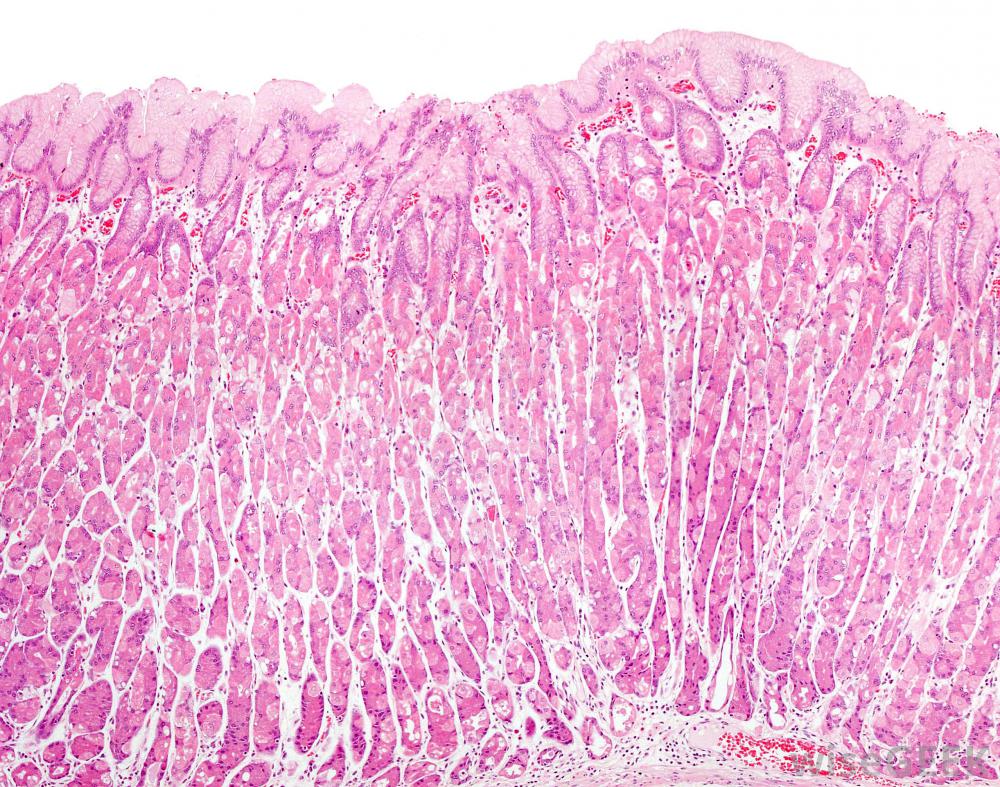

有兩種類型的組胺受體接收組胺,但它們的反應不同。H1受體參與炎癥反應,并產生過敏反應中常見的癥狀,如腫脹、打噴嚏和鼻腔分泌物增多。因此,H1組胺阻滯劑(也稱為H1拮抗劑)用于治療過敏。而H2受體則參與其中在調節胃壁細胞分泌胃酸的過程中。因此,H2組胺阻斷劑或H2拮抗劑用于防止胃酸過量產生,并用于治療消化性潰瘍和胃食管反流病(GERD)。

組胺阻斷劑調節胃壁細胞產生的酸量。